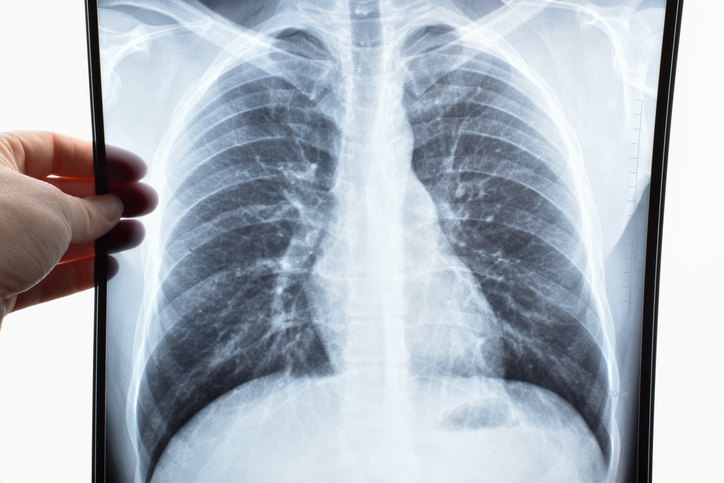

Campbell County Medical Group (CCMG) Pulmonary & Sleep Medicine diagnoses and treats diseases of the lungs and respiratory system while also evaluating and treating sleep disorders in Northeast Wyoming.

Respiratory Therapy provides comprehensive care and testing for patients suffering from breathing disorders caused by heart or lung disease. Data from tests and exams provides primary and specialty physicians with information to help with diagnosis and treatment. Read more

Pulmonary Rehabilitation is a comprehensive outpatient education and treatment program for people living with COPD or chronic lung disease to help them breathe more easily, get stronger and do more in their daily lives. Read more